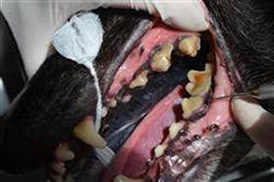

Why pets need to see the dentist too

‘The Dentist will see you now…’

If that sentence made you feel sick to the stomach, thank you for continuing to read this far! Dental health is quite an easy thing to forget about in our pets, so it comes as no surprise that most recommendations for dental surgery happen at their annual health check or vaccination, which can often be a shock for pet owners.How can I tell if my pet has a toothache?

As vets, we tend to see teeth in a much worse state than human dentists generally would; either because of the animal’s frustrating ability to hide that they are in pain, or even from their human’s own ‘dentist phobia’ – believe us, it happens! So keep an eye out for symptoms that your pet may be suffering from a toothache, such as:

- Loss of appetite

- Inability to eat

- Bad breath

- Broken teeth

- Lumps on the gums

- Facial swelling

- Rubbing their face or mouth

What happens if it’s not treated?

Now we’ve all heard of gingivitis but does anyone really take it that seriously? Gingivitis is where the tartar moves under the gum line, causing them to become inflamed, red and sore- ouch! If left untreated, it can develop into serious periodontal disease resulting in tooth loss, expensive extractions or infection affecting organs around the body.

How can it be prevented?

If the vet mentions that your pet could do with a scale and polish, don’t panic. This is the most common dental surgery we perform for pets. Just like in human dentistry, a scale and polish is performed to remove as much tartar and invisible plaque as possible to prevent any further and more serious dental disease from occurring. However, your pet will require a general anaesthetic, as they are far too wriggly to carry out even the most straight forward dentistry.

So although the thought of surgery mainly for preventative measures, like a scale and polish, may be a worrying thought, it can certainly save your pet a lot of discomfort and potentially serious health issues!